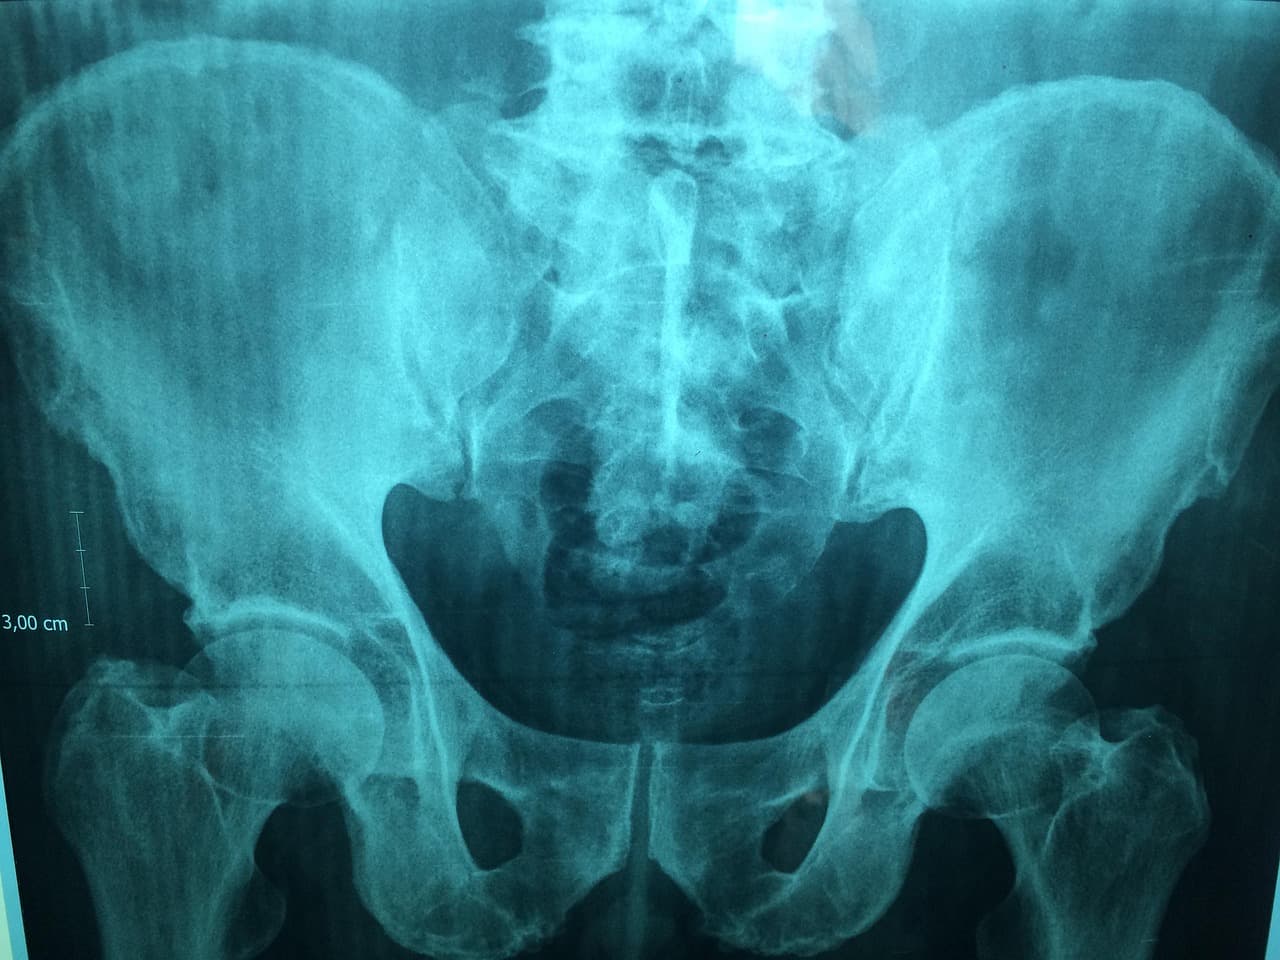

Pelvic haemorrhage in trauma remains one of the genuinely unsolved problems in acute surgery. The debate between packing and embolisation has moved from adversarial to collaborative, with the best-evidenced centres now deploying both strategies in a carefully sequenced protocol. What the evidence consistently supports is speed, systematic decision-making, and the avoidance of delay at every stage of the pathway.